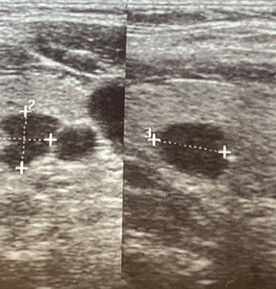

Inactive or less active areas within the thyroid gland appear as "cold" spots on the scan. Cold nodules have reduced or no uptake of the radioactive substance, suggesting lower metabolic activity which further implies an inactive gland indicating benign or malignant growths. Most thyroid nodules are cold and may require further investigation, such as fine needle aspiration biopsy (FNA), to assess for malignancy.